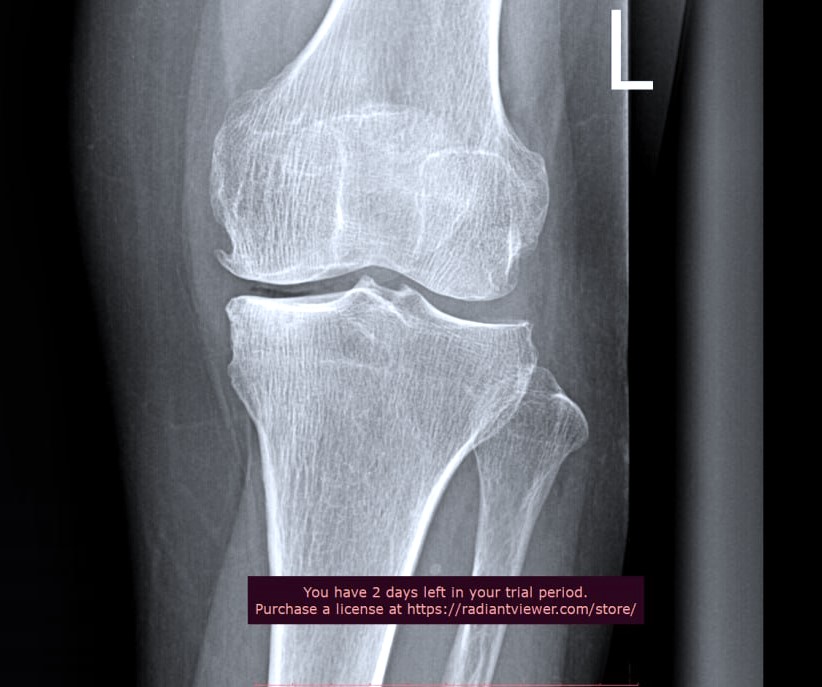

Гэмтэл согог судлалын үндэсний төвийн Насанд хүрэгсдийн мэс заслын тасгийн эмч нар дунд чөмөгний булуу шаант ясны тавцанд нэг моментоор үений гадаргуу мөгөөрс шилжүүлэн суулгах мэс засал эмчилгээг анх удаа хийлээ.

Энэхүү шинээр нэвтрүүлсэн мэс засал эмчилгээ нь үений мөгөөрсний элэгдэл /ОА II-IV зэрэгтэй/ болон үхжилт үүссэн хэсгийг авч, шилжүүлэн суулгах буюу тромбинатор /үений гадаргуу мөгөөрсийг хусаж аван үүдэл эстэй хольж, үений гадаргууг нөхөх/-ийг ашиглан сэргээснээрээ хиймэл үе суулгах мэс заслыг 5-10 жилээр хойшлуулах чухал ач холбогдолтой юм.